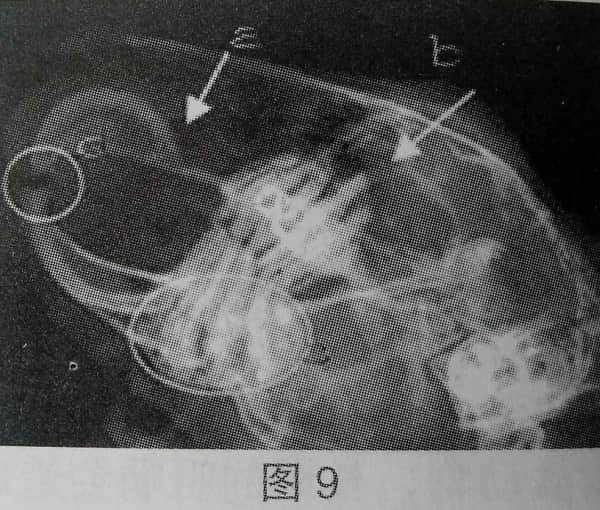

4、牙根过长

图9中a为门齿齿根过长;b为上臼齿齿根过长;上臼齿齿间距增大;C为下臼齿和下颔骨坏死,溶解;d为门齿咬合不正。